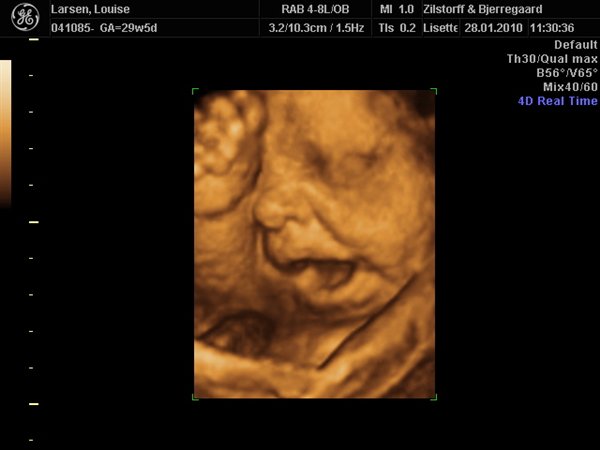

Vi har været afsted, og vi fik afvide at man anbefaler uge 29. Der er babyen stor nok til at kan se ansigts træk osv, men den er stadig så lille at der er meget fostervand rundt om babyen, hvilket er vigtig for billedernes kvalitet.... Så uge 29! Kan lige sætte et billede ind her fra vores 3d scanning i uge 29...

Zilstorff & Bjerregaard og deres klinik ligger i silkeborg, de er smadder søde og rigtig dygtige....

Vedhæftede fotos (klik for at se i fuld størrelse)